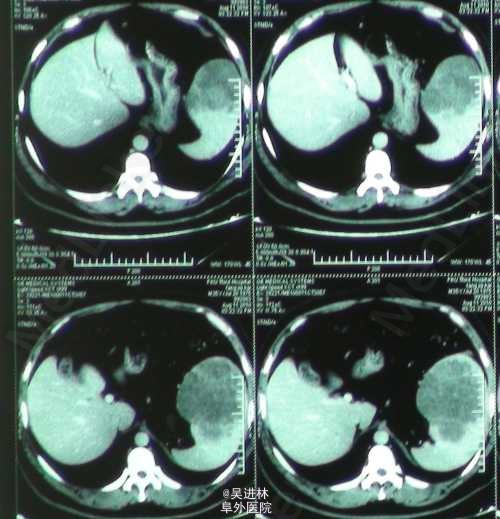

患者男,40岁,常规体检发现脾脏占位入院。主诉无特殊,无消化道症状,无贫;查体无特殊。CT表现:平扫为边界不清的低密度影,增强扫描各期均无强化。大体标本:脾脏腹侧可见一结节状肿块,周边红色,其内可见白色瘢痕。术后病理:脾淋巴管瘤。治疗:手术切脾。 拓展:淋巴管瘤可以发生在任何有淋巴管的地方,但是长在脾脏比较罕见。由于罕见,诊断困难。虽然它是良性病变,但是有病理性脾破裂的风险,最好切除,尤其是伴有临床症状的时候。